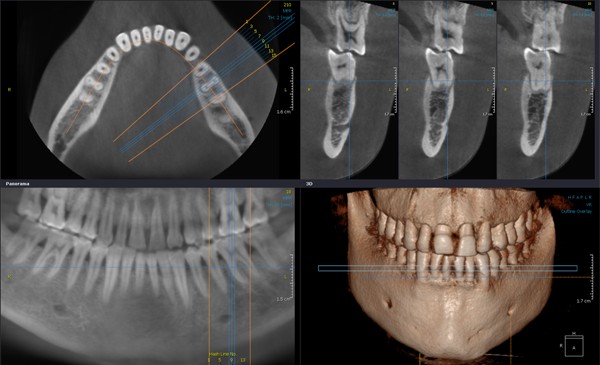

К счастью, в современной стоматологической диагностике, и в нашей клинике в частности, используются специализированные дентальные томографы. Это оборудование не только позволяет получать высокоточные снимки с толщиной среза 0,15-0,3мм, но и создавать 3D-модель сканируемой области. Имея такую информацию, стоматолог получает возможность изучить необходимый участок зубочелюстной системы под любым углом и с любой точки зрения и правильно составить дальнейший план лечения. Программа точно воссоздает все необходимые данные: форму, расположение, строение и размеры элементов челюстно-лицевой области.

Диагностика при помощи дентального томографа может использоваться в самых различных сферах стоматологии:

- Эндодонтия. Томография необходима при повторном лечении каналов зубов и проверке качества выполненных процедур.

- Ортодонтия. При исправлении прикуса врачу важно иметь сведения о состоянии суставов в различных положениях челюсти, а также расположение ретинированных и дистопированных зубов.